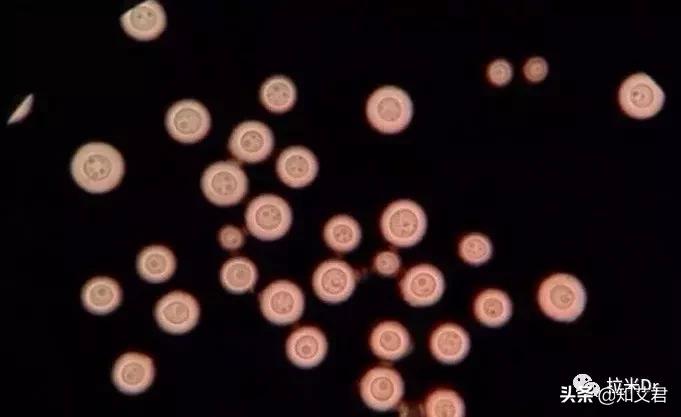

2.隐球菌病

隐球菌病是一种潜在的致命真菌病,每年影响超过100万人。在HIV感染者中,隐球菌病常常发展为隐球菌性脑膜炎,这种情况会影响中枢神经系统,是当今艾滋病患者的第三大常见并发症,多见于CD4+T细胞计数<50个/μl的患者。在应用HAART以前,艾滋病患者中隐球菌脑膜炎发生率为5~10%,HAART广泛应用后其发生率明显下降,但是艾滋病合并隐球菌脑膜炎的预后差,即使在发达国家病死率仍高达10~30%。

美国疾病控制和预防中心(CDC)将肺外隐球菌病(包括隐球菌性脑膜炎)列为艾滋病定义性疾病。典型的隐球菌性脑膜炎的症状包括: